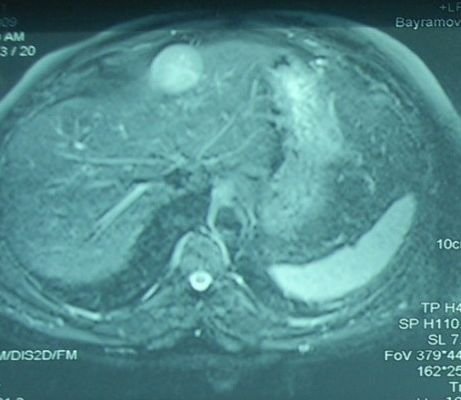

- Diaqnozu dəqiqləşdirmək üçün Qc venaları yoxlanılmalıdır. Bunun üçün dopler USM, KT-angioqrafiya, MRT-angioqrafiyalar və ya kontrastlı venoqrafiya edilir.

- Görüntüləmədə Qc venalarının trombotik tutulması diaqnozu dəqiqləşdirən əlamətdir.

Baddi-Kiari sindromu böyük qaraciyər venalarının tıxanması nəticəsində meydana gələn venoz durğunluqdur, qaraciyər venaları ilə yanaşı aşağı boş venada da tıxanma ola bilir. Tromboz, fibroz, membran və infiltrasiya (şişlər, iltihab) ən çox rast gələn səbəbləridr. Erkən mərhələlərdə kəskin hepatit və kəskin qaraciyər yetməzliyi, xroniki mərhələdə sirroz və PH meydana gələ bilir. Diaqnozu üçün tomoqrafiya və kontrastlı angioqrafiya lazım gəlir, Qc venalarının trombotik tutulması diaqnozu təsdiqləyir. digər xarakterik əlaməti birinci seqmentin hipertrofiyasıdır. Erkən mərhələdə dekompressiya (cərrahi və stend) sirroz əmələ gəldikdə isə transplantasiya ön planda tutulur.

Qaraciyər venalarının görünməməsi, kontrastlaşmaması və ya trombla tıxanması.

- Görüntüləmədə qaraciyər venalarının tıxanması, I seqment hipertrofiyası ola bilər (xroniki forma);